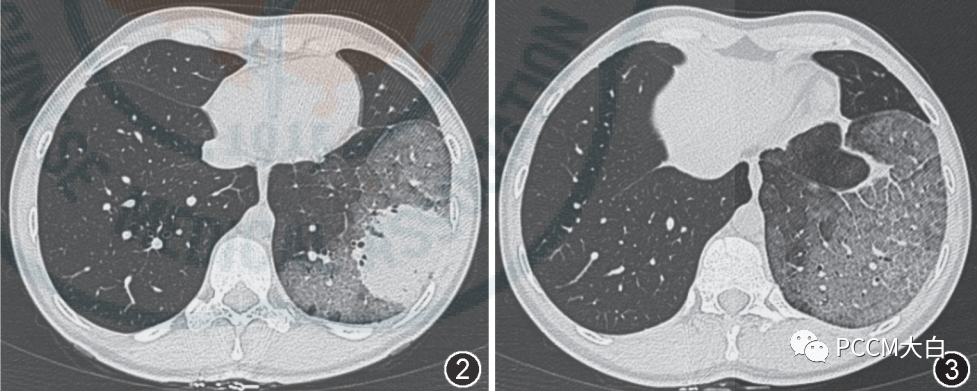

晕征是指肺部CT上表现为围绕结节或肿块周围的略低于肿块密度而又高于肺实质密度的环形磨玻璃影。晕征最早用于描述局灶性侵袭性曲霉菌病灶周围出血的征象,被认为是肺部真菌感染的特异性影像表现。晕征中磨玻璃样影通常和结节出血相关,这些结节出血的机制包括:出血性梗死、血管炎、支气管动脉瘘以及坏死等。当然了,磨玻璃影还可以由肿瘤或炎症浸润周围肺组织造成。

肺隐球菌病:下图。肺隐球菌病的影像学表现多种多样,缺乏尤特异性。免疫功能正常者常使病灶局限形成肉芽肿结节,因此胸部 CT常见表现为单发或多发的结节肿块影,直径大小不等,边界清楚,可有分叶及毛刺,容易误诊为肺癌和肺转移瘤。其次还可表现为斑片浸润影、实变影和偏心后壁空洞。病灶多位于中下肺野外带分布,可伴有支气管充气征、晕征 。